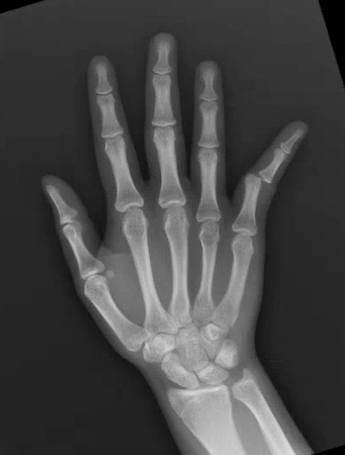

A 13 year old female presents with right 5th digit pain and deformity after she hyperextended her finger while catching a basketball. What's the diagnosis? (scroll down for answer)

Answer: Proximal interphalangeal joint dislocation